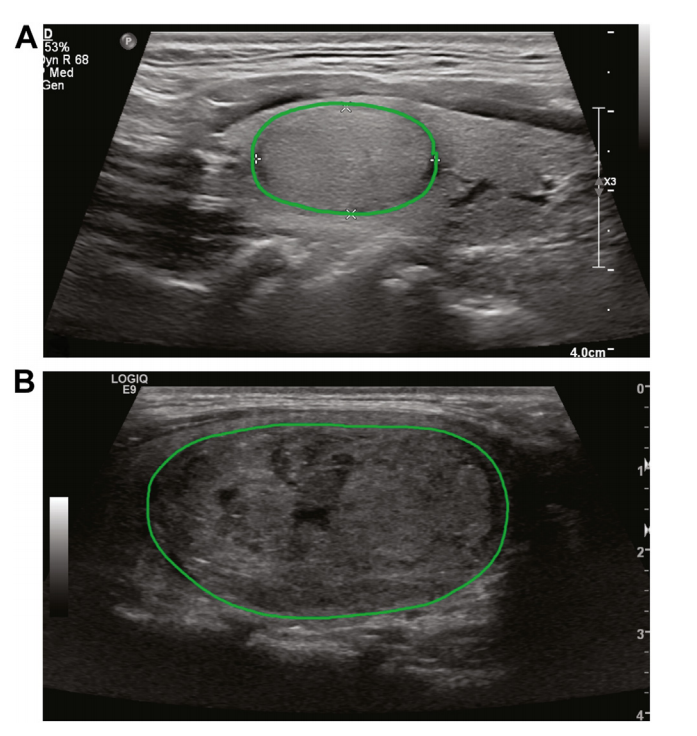

Figure 1. Two examples of annotated ultrasound imagesd(A) adenoma; (B) carcinoma. Ultrasound images were cross-referenced with pathology reports to identifynodule of interest in each patient. All images that had nodule in view were manuallyannotated as shown to indicate region of interest ROI.

图1. 两个标注过的超声波影像示例(A)腺瘤;(B)癌症。超声波影像与病理报告进行了交叉参考,以确定每个患者感兴趣的结节。所有展示结节的影像均已手动标注,如图所示,以指示感兴趣区域(ROI)。